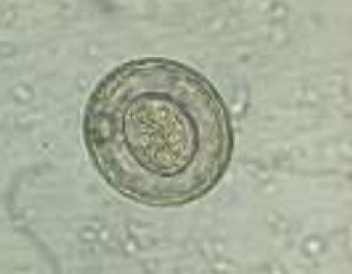

In breve i coccidi sono Protozoi, tipicamente organismi unicellulari. Quelli di interesse veterinario sono parassiti obbligati che sfruttano le cellule intestinali per nutrirsi e riprodursi; facendo questo portano al danneggiamento della cellula stessa con sua conseguente morte.

Animali debilitati e abbattuti, in base alla specie di coccidi le feci variano dal diarroico bianco/marrone al giallo, con o senza presenza di macchie di sangue. Nei pulcinotti tra le 3 e le 8 settimane di vita questa parassitosi può portare a mortalità elevate. Gli animali con cloaca imbrattata, abbattuti e con meno stimolo alimentare andrebbero isolati procedendo poi ad un esame parassitologico per flottazione (in cui si evidenzieranno le oocisti presenti in caso di positività). Se possibile sarebbe ideale spostare gli animali su rete per un mese, in modo che non entrino in contatto diretto con le feci e sia più difficile la reinfezione mentre le oocisti ancora presenti nel box di provenienza, che andrà pulito a fondo, andranno incontro a decadimento.